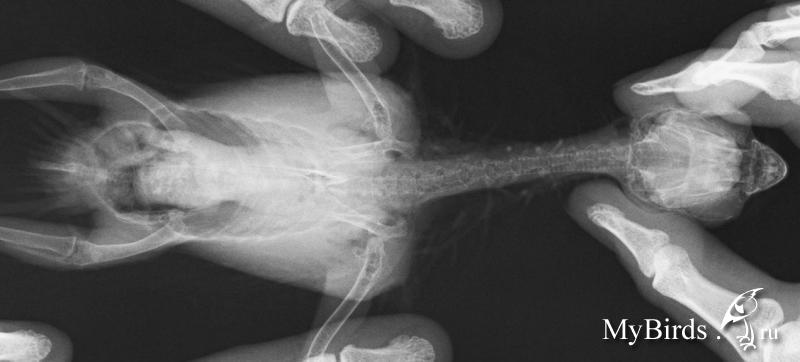

NikaK Опубликовано 9 сентября, 2013 #1 Опубликовано 9 сентября, 2013 (изменено) Розеллы мальчик и предположительно девочкамальчик - 11 лет, девочка год с небольшимрацион содержание и прочее - в темеhttp://www.mybirds.ru/forums/index.php?sho...&hl=розелла сейчас мне нужен только ответ по конкретным рентгенам. большие изображения лежат вот тут ftp://ftp.batteryteam.ru/pdf%20to%20print/Мальчик 11 лет Девочка (может быть нет) 1,5 года вопрос - можно ли по этим снимкам подозревать аспергиллёз?заранее спасибо за ответ. Изменено 9 сентября, 2013 пользователем NikaK

Zosia Опубликовано 9 сентября, 2013 #2 Опубликовано 9 сентября, 2013 У саммца (Жорка,да?) точно что-то есть, и одно легкое нехорошо вздуто. У самки если и есть (в центральной части затемнение)- видно плохо. Анализ нужно делать,причем 3 раза.Аспергиллез по трем анализам ставят,два должно быть положительно. Т.к. лечение его а)- дорогое (очень), б)- токсично, требует параллельно несколько препаратов- для прикрытия.

Zosia Опубликовано 10 сентября, 2013 #10 Опубликовано 10 сентября, 2013 Так.Поговорила с теми,кто вас сейчас ведет. Мое мнение- до аспергиллезного диагноза вам надо исключить ТУБЕРКУЛЕЗ,т.к. ваша упавшая иммунка, и то что на ваших птиц все садится, и то что одна птица явно заразилась от второй (а такого в ДОМАШНИХ условиях при аспергиллезе практически не бывает,зато бывает при туберкулезе) и специфически вздутое лоегкое, и сетчатый рисунок на нем- может говорить именно о Т, а не о А. исключить (или подтвердить) Т легче,чем А. Это сделают в Горветлаборатории.Я созвонилась с ними, и созвонилась в Мариной Лешковой (Центр, вы в четверг илите- будете сдавать кровьЮ смыв и,возможно,фекалии- на исключение туберкулеза. До результатов анализа- максимально птицу иммунить (всем чем можно- от катозала до фоспренила), только если прмиенять будете параллельно два иммуностимулятора- дозы давать половинные по каждому. А иммуномодулятор (деринат например) или иммунопротектор (катозал)- без изменений.Дозы "стандарт" по иммуностимуляторам: 0,02 мл на каждые полные 50 граммов веса птицы суточноИммуномодуляторы- 0,054 мл суточно на каждые 50 граммовиммунопротекторы- 1:200 в поилку.исключить все фрукты и овощи (ВРЕМЕННО).Никаких витаминов.

Zosia Опубликовано 10 сентября, 2013 #12 Опубликовано 10 сентября, 2013 тогда я правильно не начала давать назначенный орунгал Н.С. так там в четверг будет принимать Лешкова? А с Волгиной мне как объясниться?) Точно так же. Наталья Сергеевна сейчас на конференции в НовоСибе, но она будет в курсе. Я могу объяснитьна чем базируется мое мнение(как я М уже объяснила).1. Изначально была нездорова одна птица. Вторая заразилась от неё. При аспергиллезе такого в условиях квартиры или квартирного вольера не происходит (у вас же не капает по стенам,не ползет плесень по углам, не летает гуано и сопли-как на прицефермах). А вот туберкулез вполне воздушно-капельным путем даже в квартирных условиях мог передаться.2.Иммунка у вас упала уже полтора года как. На аспергиллезе птиц бы уже помер.На туберкулезе может жить долго- если постоянно поддерживать антибиотиками (даже непрофильными),иммуностимуляторами.3.У самца резко вздуто одно легкое- по клинике детей это характерно для туберкулеза. Хотя А тоже может такое дать(агрессивный), но опять же- птиц бы уже ушел за радугу.4.Мозаичный рисунок легких... 5.У самки по центру что-то.похожее на аспергилломы, виднеется.Но ровно так же это может быть и туберкулемы. Ответ даст только анализ. На анализ будет взята кровь,мазок,помет.Проводить будут в Горветлаборатории (ул.Юннатов 16 а), я с ними созвонилась уже. В принципе можно было бы обойтисьь гораздо меньшими проблемами, если бы была туберкулиновая проба.НО! Нет сейчас в Москве малых фасовок птичьего пробника,только по 38 кг (на птицефермах), а отщипнуть не дают. А так- можно было бы поцарапать кожу,нанести пробу и посмотреть результат. Хотя конечно бывают наверное какие-то варианты аспергилл, нетипичные, малоагрессивные, при этом высокоустойчивые к внешним факторам и передающиеся прямо по сухому воздуху московских квартир (26,30% влажности в отопительный сезон). Как известно,только гильотина дает 100% однозначный результат.если будет туб- его лечить уже чисто антибиотиками.с прикрытием системными антмикотиками. лечат долго, но хоть уверенно.

NikaK Опубликовано 12 сентября, 2013 Автор #18 Опубликовано 12 сентября, 2013 (изменено) Так, была на приеме, взяли кровь, дали две пробирки для помета. Но...позвонита в горвет на юннатов - они сказали, что:1. анализ ТАКОЙ можно сдавать ТОЛЬКО при направление наблюдающего врача...они конечно не откажут взять, но типа это на них вешается ответственность лишняя, и им это не очень то хочется. сказали под паспортные данные - ок, фиг с ними.2. КРОВЬ - НЕ берут на туберкулез... берут смыв из глотки, помет, и что-то еше, я от удивления забыла. Получается что у меня только 1 из 3 анализов... достоверность видимо равна ....и еще посмотрели еще пристально Н.С. и Мария рентген обоих - приказывают лечить орунгалом (+ преднизолон для триши с полиурией, +пробиотик, +АЦЦ в поилку, +мовалис 2 недели, + иммунофан для обоих все кроме 1) ... я еще больше в растерянности... Изменено 12 сентября, 2013 пользователем NikaK

Zosia Опубликовано 15 сентября, 2013 #31 Опубликовано 15 сентября, 2013 сегодня второй день по вышеописанной схеме - ттт! - все вроде без проишествий... надеюсь и дальше так же будет. а аспергиллез- -так же, ничем 100% не подтверждается у живой птицы? Подтверждается, но не всегда.Кишечный- легко,легочный- очень трудно. Рентгеноскопически- при наличии аспергиллом явных (тут как раз обязательно дифференциировать от тубекулеза,т.к. он дает туберкуломы,похожие немного на аспергилломы).Вздутые легкие и мешки,наличие жидкости в них,тяжелое и мелкое дыхание, ослабленность,упавшая иммунка.Т.е. часть симптомов- косвенная и может быть неоднозначна.(Микоплазмоз напрмиер,который у вас исключали в первую очередь).